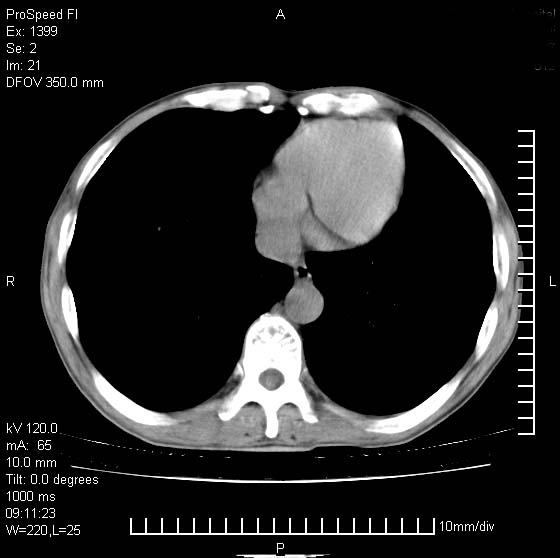

以下是引用卜一在2007-1-19 9:55:00的发言:[br]左肺沿胸膜下巨大肿块影,边缘呈分叶征,纵隔内见肿大淋巴结,右肺内另见一不规则结节影 .考虑:左肺周围性肺癌伴纵隔 右肺内转移.

以下是引用rgsyyf在2007-1-19 11:05:00的发言:[br]左肺上叶见形态不规则巨大软组织肿块影,边缘呈分叶征,纵隔内隆突下见肿大淋巴结,右肺内另见一不规则结节影 .考虑:左肺周围性肺癌伴纵隔即右肺内转移.